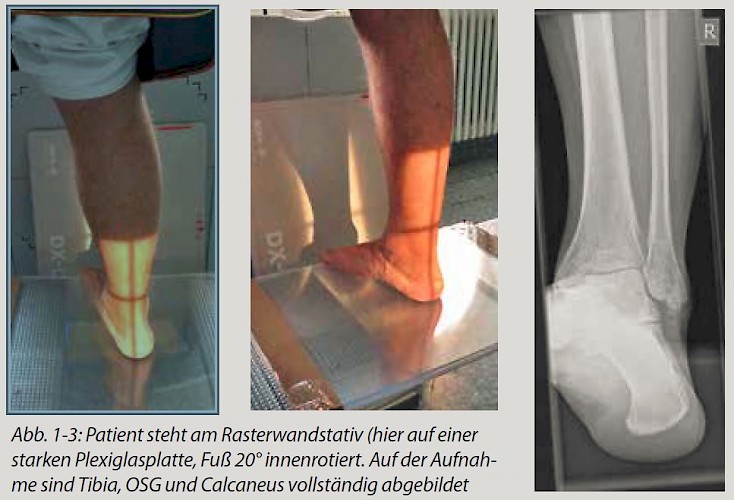

- Der Patient steht mit der Brust zum Rasterwandstativ auf einem trittsicheren Hocker.

- Fuß und Unterschenkel um 20° nach innen rotiert (Abb. 1 und 2).

Das Fersenbein lässt sich wie zur axialen Aufnahme identifizieren. Außerdem kommt das obere Sprunggelenk zur Darstellung, so dass eine Achsenbestimmung Unterschenkel-Calcaneus möglich ist (Tibia, OSG, Calcaneus muss vollständig für die Winkelmessung abgebildet sein, Abb. 3).

Die Kolleginnen aus Erlangen lagern den Patienten laut ihrer Referenzdatenbank auf einer Plexiglasscheibe, die zwischen einem Gestell zu liegen kommt. Der Fus steht frei auf dem Plexiglas, so dass der Hocker bzw. eine anderweitige Unterlage die Darstellung auf dem Röntgenbild nicht stört.